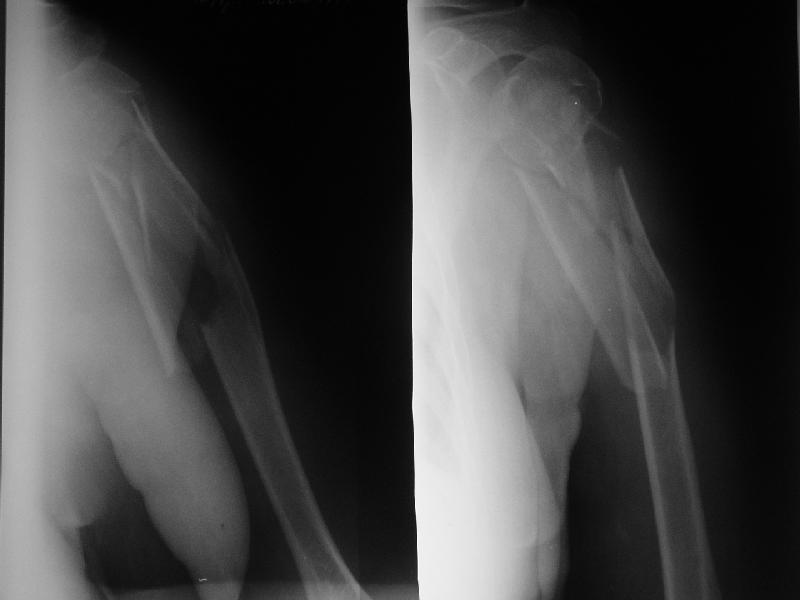

Re: Оскольчатый перелом плеча

Доминирующая ли рука и какая профессия?

Если выбор на интрамедулярный штифт, я бы сделал КТ головки, информация необходима для определения вовлечения головки в перелом, имеется опасность

расколочения и для ориентира расположения блокирующих шурупов.

Другой вариант, небольшой гипс на локтевой сустав как груз для тракции, повязкой за кисть выше-вниз можно контролировать сгибание и разгибание на место перелома, небольшая отводящая подушка в живот (у женщин молочная железа в зоне перелома

создает варус)сделать ренген снимки через одну недели. Перелом низкоэнергетический, может быть, без операции обойдется.

"Рука не доминирующая, но тоже нужна" - А.Н. Челноков. Больная уже лечилась консервативно в гипсовой повязке и на вытяжении, в настоящее время настаивает на оперативном лечении.

Есть и другие косые снимки, на которых не определяется вовлечение головки, если успеем - сделаем КТ. Спасибо за интерес к нашему случаю.

Ув. коллеги. Интересно, насколько разрушена головка, особенно ее артикулирующая поверхность, может для начала сделать КТ головки.

На счет операции - стоит ли ее вообще делать, куда Вы собираетесь забить стержень, на расколете ли головку, если она еще целая. В любом случае Вы

не добъетесь стабильной фиксации, прийдеться иммобилизировать где-то на месяц. Вопрос: какова будет функция после травматичной операции, а она

имеенно таковой будет и последующей иммобилизации. ВЧКДО сделать не получиться - не за что зацепиться.